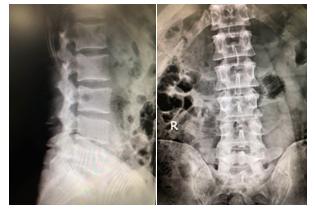

1、X光(X-ray、X射线)

X光是现在最常见、最普遍的一种医学检查。在骨科工作中,其最主要的作用是让临床医师们观察患者的骨性结构。在大部分情况中,X光仅能观察的腰椎椎体的结构,椎管内的神经形态、椎间盘的具体情况等都没办法观察到。一般X光可以明确的疾病有椎体滑脱、椎体不稳、椎体峡部裂以及鉴别一些椎体骨折等,但需要注意的是,椎骨骨折虽然在X光上可以观察到,但大多时候还需要MRI检查去明确其是否新鲜骨折,否则难以拥有准确的诊断。